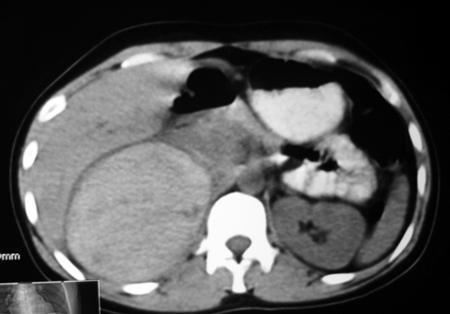

以下是引用卜一在2009-4-23 15:43:00的发言:[br]考虑右肾包膜下血肿,不排除占位病变伴出血可能,建议进一步检查。